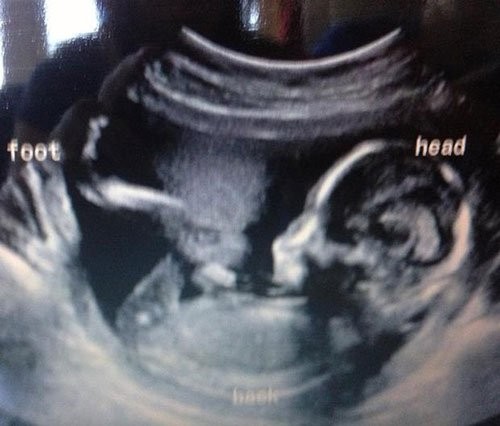

Bebeğinizin olacağını öğrendiğiniz ve büyük bir heyecanla doktorun yolunu tuttuğunuz o anı hayal etmeye çalışın. Şimdi de ultrasonda bebek yerine bir ördek gördüğünüzü düşünün. Merak etmeyin, aslında sadece “pareidolia” sendromunu yaşıyorsunuz. Yani gördüğünüz alelade şekilleri anlamlandırmaya çalışma hali… İşte bebek ultrasonlarında çekilen ve bazı anne babalara mini kalp krizi geçirten bebek fotoğrafları!

Ördek